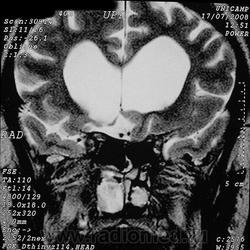

Фронтоэтмоидальное энцефалоцеле.

Отдел патологии, школа медицинских наук.

Государственного Университета Кампинас (UNICAMP).

Кампинас, Сан-Паулу, Бразилия.

Цефалоцеле